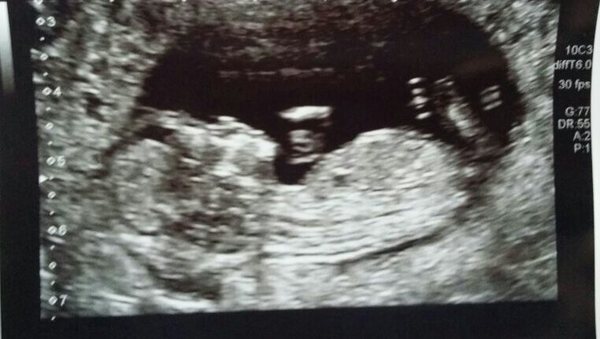

July 2015 - more and more beans are seen on scans

Second Charlie & Tilly. Lovely scan picture Miss Smile

Our scan went well today. A very wriggly little baby, either dancing or hiccuping Smile Baby measured ahead at 12+3 and due date is now 11th July. Got lots of pictures, about 10! Baby is 8cm including its little legs, amazing Smile. 20 week scan is on 24th Feb.

Sherbet38 ahh lovely pic!